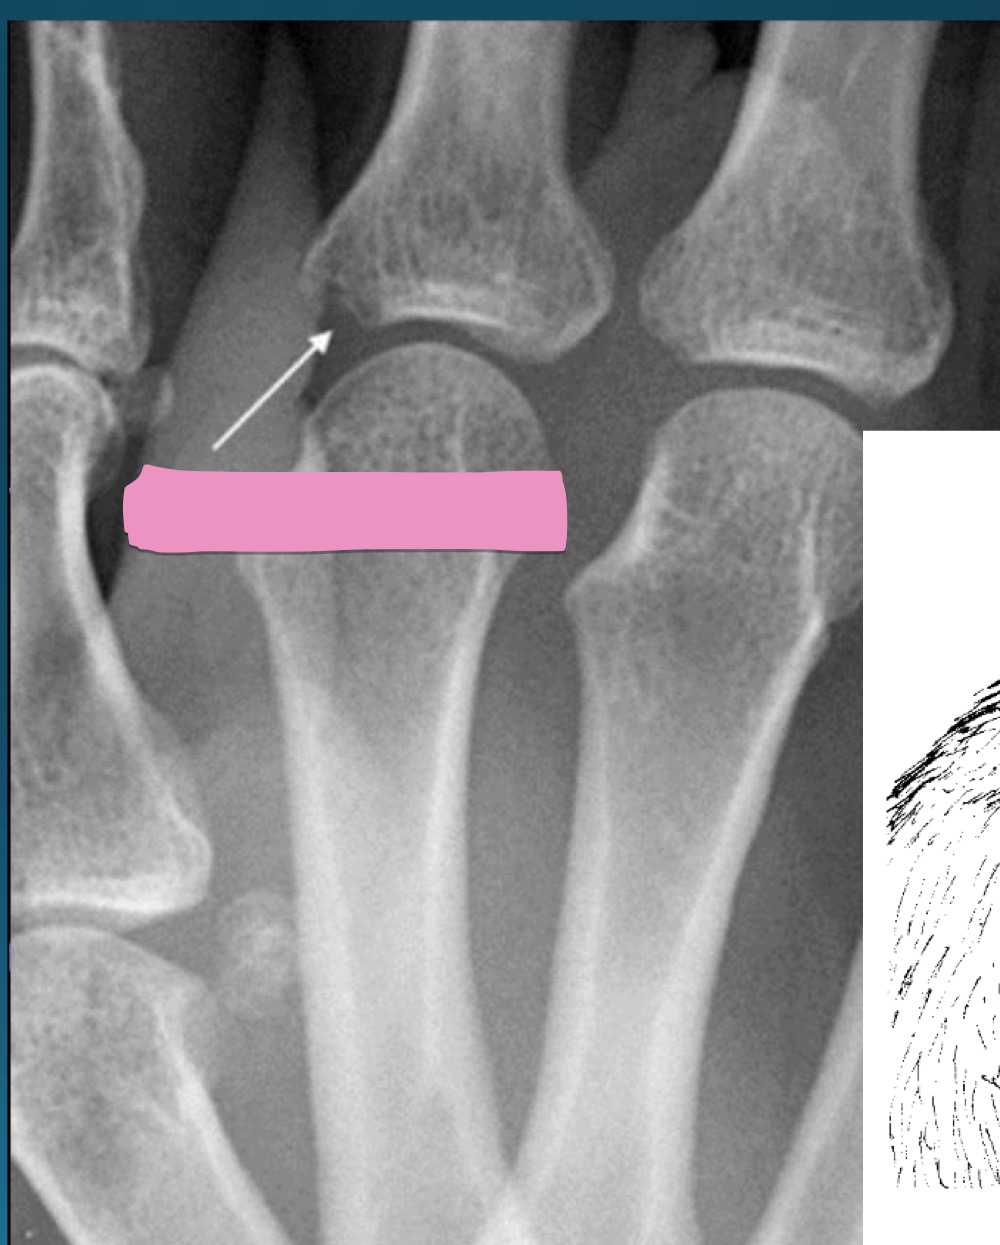

what are the findings in this image?

erosive osteoarthritis

waht are the features denoting erosive osteoarthritis on radiograph?

central erosions creating gull wing sign

EOA likes what joints?

DIP, PIP, 1st CMC